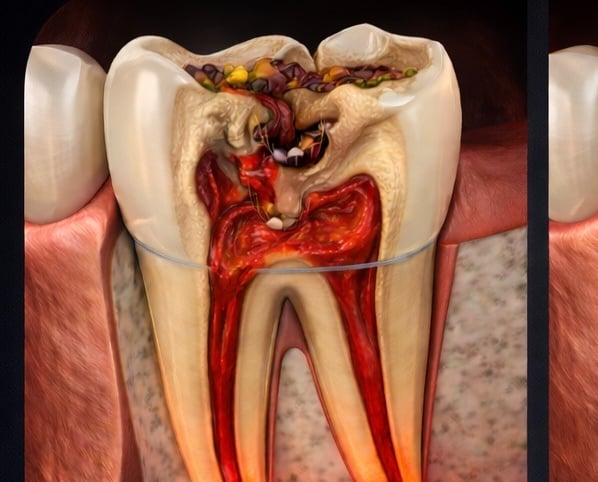

Root canal treatment removes infected or damaged pulp from inside a tooth. The pulp contains nerves and blood vessels, and infection can cause pain, swelling, or abscesses. During the procedure, the dentist cleans out the infection, shapes the root canals, and fills them with a safe material. Finally, the tooth is restored with a crown or filling to protect it. Root canals prevent infection from spreading and help keep your natural tooth

Cleaning the pulp – remove infected tissue from inside the tooth

Shaping & filling – shape canals and fill with biocompatible material